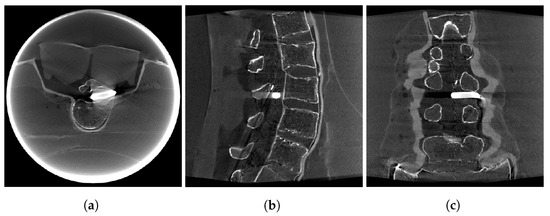

2. Materials and Methods

3. Results